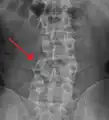

A burst fracture of L4 as seen on plane X ray -

A burst fracture of L4 as seen one plane X ray -